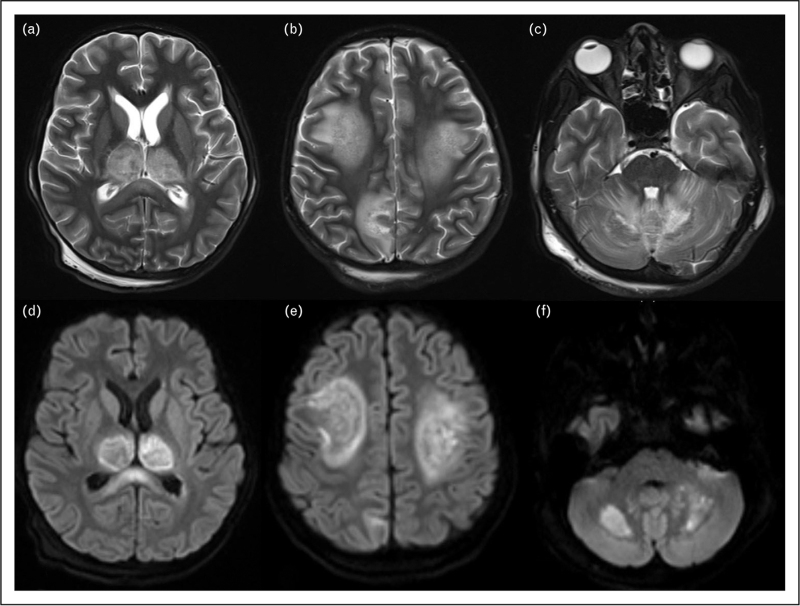

Recent findings: Recent research has improved our understanding of dengue encephalitis and the neurotropism of the dengue virus in regions such as the thalamus, basal ganglia, and cortex. Notable MRI findings include the 'double doughnut' sign and microhaemorrhages, although these findings are nonspecific and may also appear in other flavivirus encephalitides. A definitive diagnosis requires a positive cerebrospinal fluid (CSF) PCR for the dengue virus, often combined with antibody testing in both CSF and serum. Additionally, elevated levels of IL-6 and TNF-α in CSF indicate enhanced inflammatory responses, which strengthens the early identification of dengue encephalitis and informs potential management strategies.

Summary: Evidence affirms the neurotropic nature of dengue, confirmed by positive CSF PCR results. MRI typically reveals T2 hyperintensities in specific brain areas, along with the presence of micro-haemorrhages, and the 'double doughnut' sign. Recent advancements in diagnostics include analysing CSF dengue antibody indices and neuroinflammatory markers. Dengue serotypes 2 and 3 exhibit heightened neurovirulence, with seizures occurring in 30-40% of cases. While supportive management with fluids is crucial, a subset of patients may benefit from intravenous, immunoglobulin (IVIG) and steroids. Early identification of dengue encephalitis could significantly improve patient outcomes.